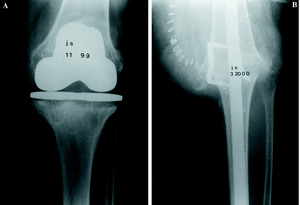

Entre diciembre de 1991 y marzo de 2000 se realizaron 21 artrodesis de rodilla mediante enclavado endomedular. El estudio está basado en el análisis retrospectivo de estos procedimientos y su evolución. De los 20 pacientes, en un caso se realizó artrodesis en ambas rodillas aunque no coincidieron en el tiempo; 15 fueron mujeres. La edad media, en el momento de la cirugía, fue de 67,8 años (mínimo 17 y máximo 82 años). La causa de la artrodesis fue el fracaso de la artroplastia en 18 casos, un osteosarcoma en metáfisis femoral distal en un varón de 17 años, una gonartrosis severa en una paciente con obesidad mórbida y artroplastia de la rodilla contralateral (Fig. 1) y, por último, una gonartrosis en un miembro afecto de poliomielitis.

Figura 1. Paciente con obesidad mórbida y artroplastia de rodilla contralateral. A: Radiografía preoperatoria. B: Radiografía a los 3 años de la cirugía, consolidación.